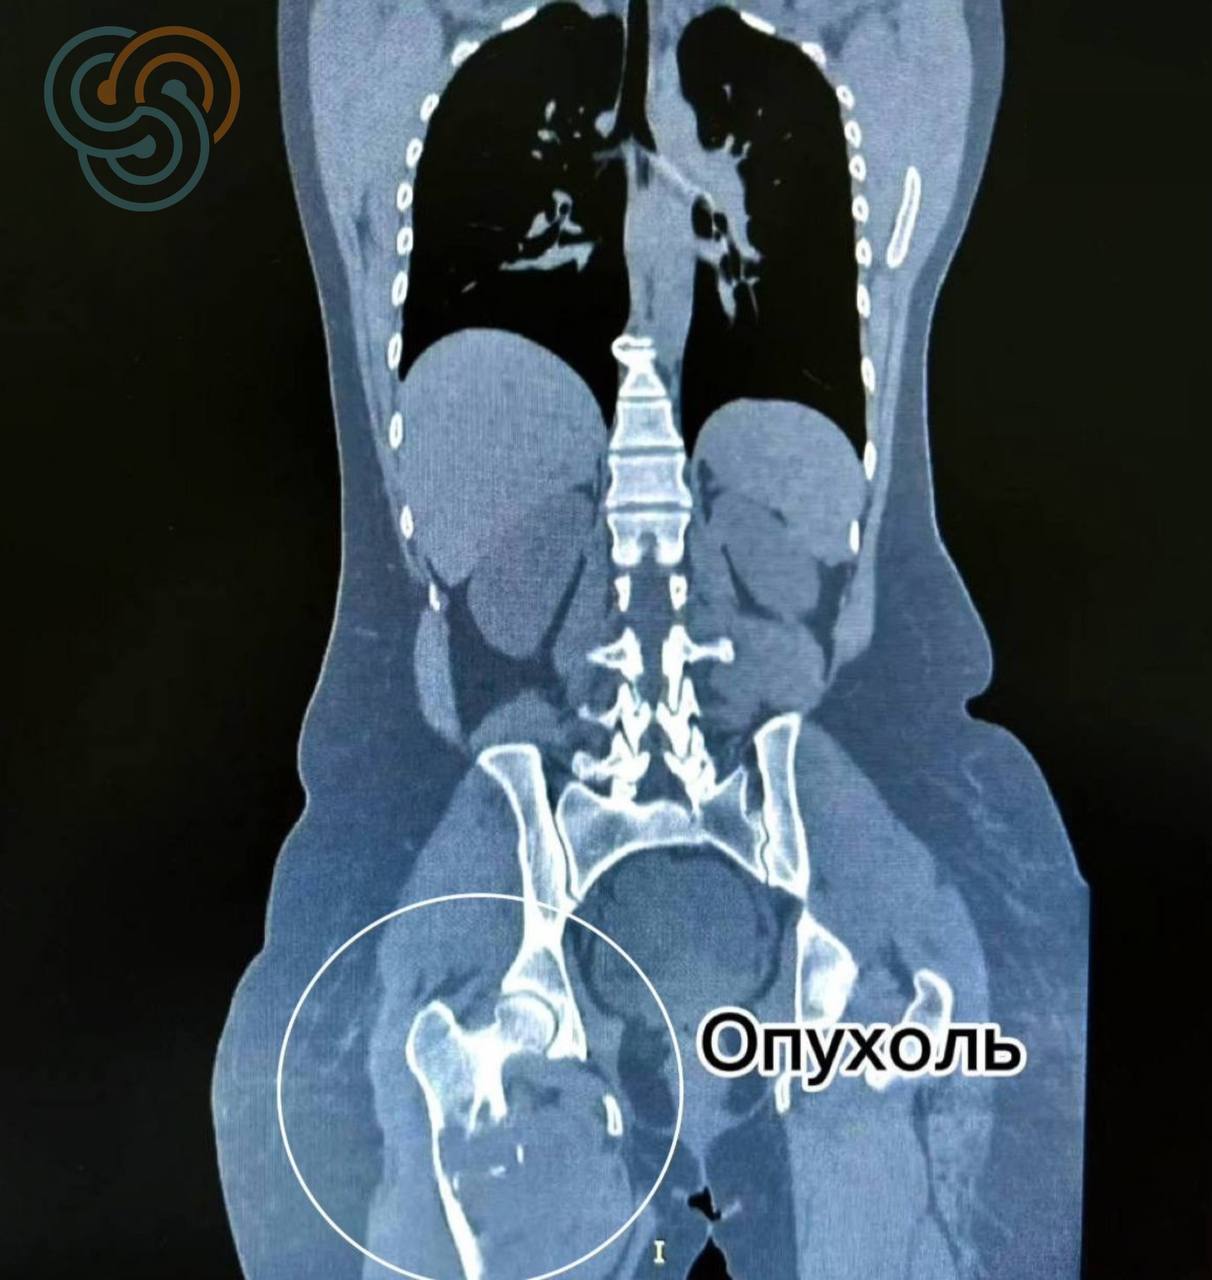

Пока биопсийный материал направляли в федеральный центр для уточнения диагноза, болезнь не ждала. Опухоль разрушала бедренную кость, и вскоре произошло одно из самых тяжёлых осложнений — патологический перелом.

В подобных ситуациях медицинская тактика в большинстве случаев предполагает ампутацию — решение, которое позволяет остановить процесс, но серьёзно влияет на качество жизни пациента.

«Объём поражения был крайне большим — фактически затронута вся бедренная кость. В большинстве подобных случаев на этом этапе пациент теряет ногу. Здесь нам удалось выполнить радикальное хирургическое вмешательство с сохранением конечности».

В декабре была выполнена операция, которая ранее не проводилась в Татарстане: полная замена поражённой бедренной кости с тотальным эндопротезированием тазобедренного и коленного суставов.